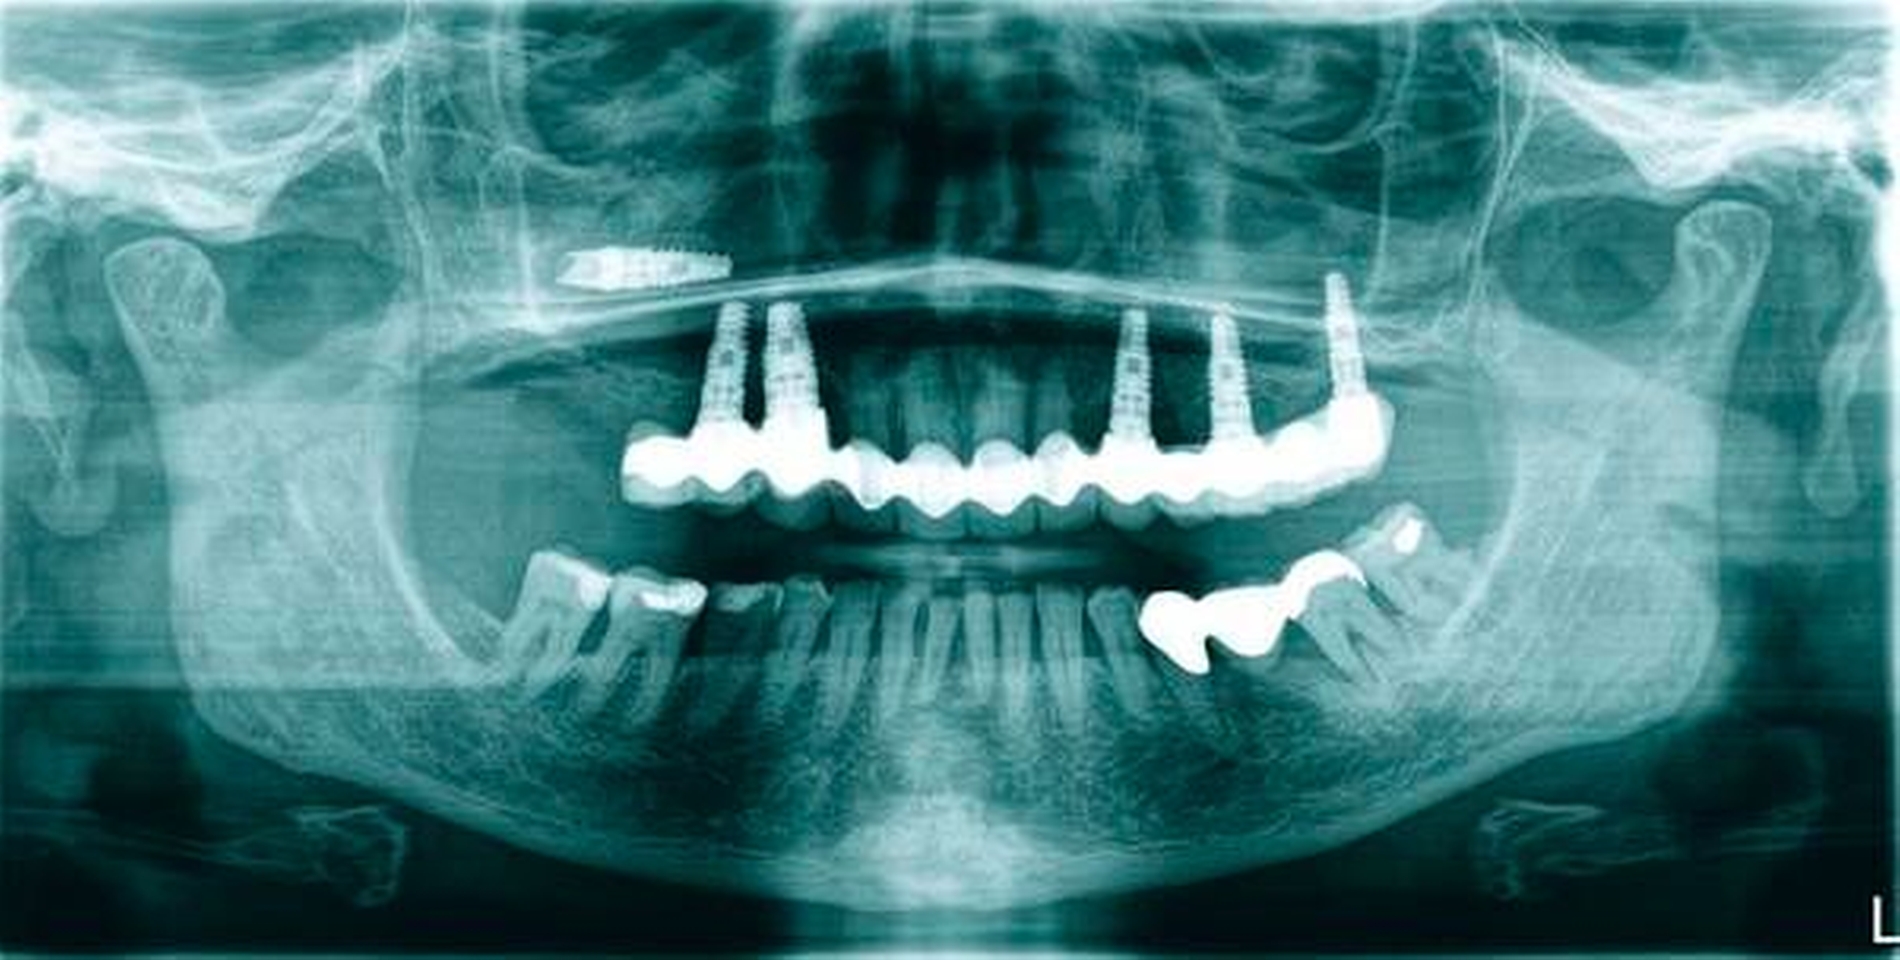

Die zweite Patientin, 75 Jahre alt, zeigte eine medikamentös eingestellte arterielle Hypertonie in der allgemeinen Anamnese. Sie hatte 2011 beidseits eine externe Sinusbodenelevation erhalten. Auch hier wurden Knochenersatzmaterial und autologer Knochen verwendet. Im Jahr 2012 folgte die Implantation von Titanimplantaten Regio 17, 14, 13, 23, 25, 27 für eine festsitzende Oberkieferversorgung.

Eine röntgenologische Routineuntersuchung ihres Zahnarztes ergab im April 2017 die vollständige Luxation des Implantats 17 in die Kieferhöhle direkt aus der prothetischen Versorgung heraus (Abbildung 3). Die Patientin hatte ebenfalls keine klinischen Beschwerden.

Im Fall des luxierten Implantats wurde in Intubationsnarkose ein Knochendeckel angelegt (Abbildung 8) und das Implantat über diesen Zugang extrahiert (Abbildungen 9 und 10).

Klinisch zeigten sich ausgeprägte polypöse Schleimhautveränderungen. Die ehemalige Insertionsstelle des Implantats war vollständig verschlossen. Nach Entfernung des Implantats, Reposition und Fixation des Knochendeckels wurde der Mukoperiostlappen in Ursprungsposition vernäht.